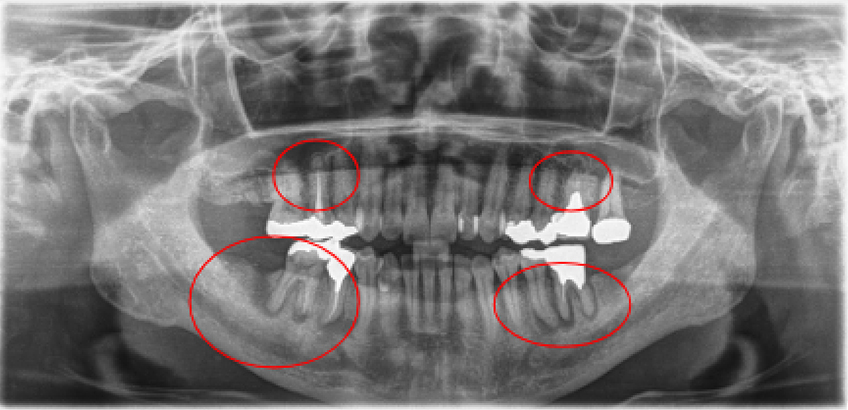

治療前治療後

| 治療内容 | インプラント奥歯1本・根管治療6歯 |

|---|---|

| 患者様の年齢 | 54歳 |

| 患者様の性別 | 女性 |

| 治療期間 | 2年 |

| 治療回数 | 根管治療合わせて70回程度 |

| 治療費用 | インプラント1歯 50万円/根管治療6歯 30万円 |

| 治療で得られるメリット |

|

| 治療する際に起こる リスク・副作用 |